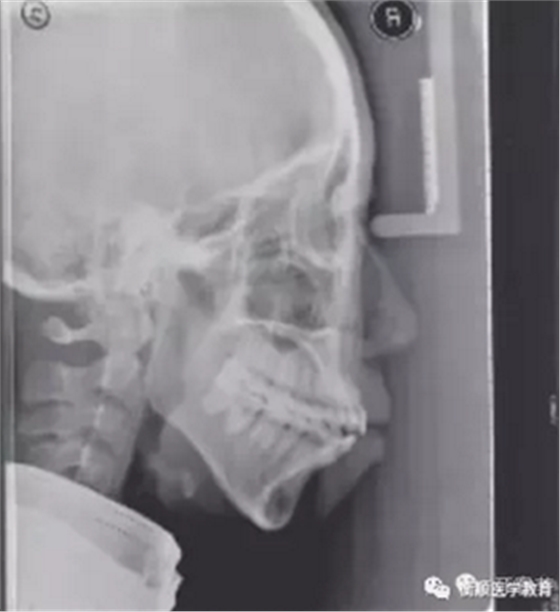

图2 治疗前头颅侧位片